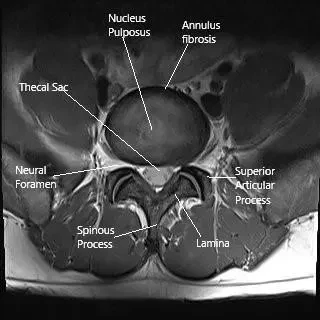

MRI of the lumbar spine in the axial section.

How the Body Part Normally Works? (Relevant Anatomy)

The spinal cord runs through the spinal canal, surrounded by protective layers called the meninges and the vertebrae. Nerves branch off from the spinal cord to transmit signals to the rest of the body.